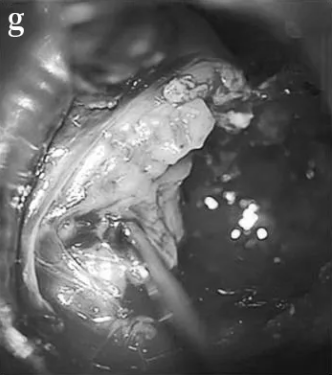

STEP 03:对CPA区肿瘤部分进行内部切除。

STEP 04:肿瘤已完全切除,解除脑干压迫。

STEP 05:面神经被肿瘤浸润, 在图像上可以看到近端、残端有一些附着的肿瘤(箭头)。

尽管无法识别神经纤维,但电刺激整个内侧肿瘤部位可激发动态的面部肌电图反应,这也证实肿瘤并非术前的听神经瘤,而是面神经鞘瘤。同时,考虑到Elsa的年龄较小,代偿能力较强,在CPA区的面神经重建术后,面部功能恢复程度非常高,而一旦残余肿瘤,孩子很可能会反复复发,不得不多次手术或放化疗,备受折磨。因此,在权衡各方利弊后,巴教授决定牺牲面神经,最终成功实现了肿瘤全切。